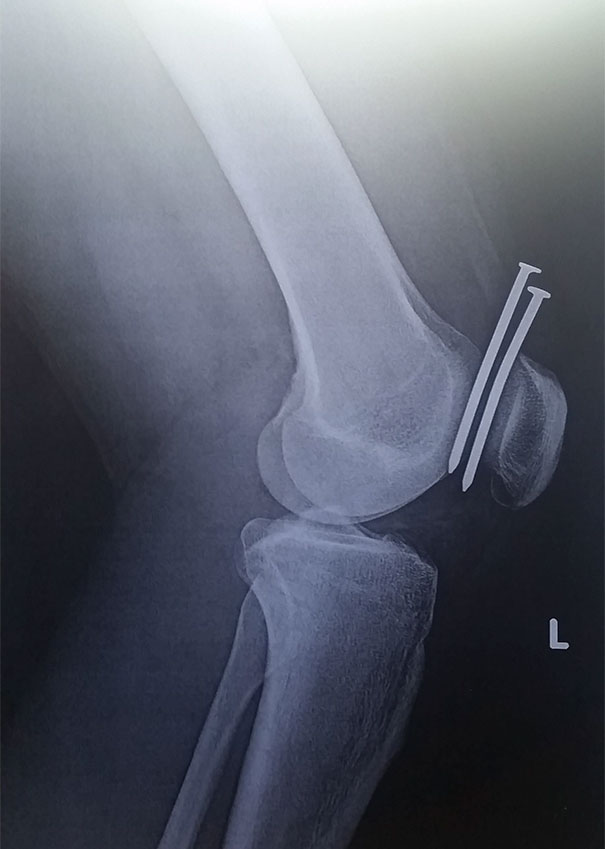

This Guy Had Two Nails From A Nail Gun Hit His Leg, And They Both Missed His Femur And His Kneecap